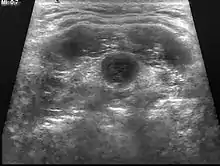

| Diagnostic method | Ultrasound[1] |

It develops from tissues left over after the formation of the thyroid gland during early development.[1] Diagnosis is usually by ultrasound.[1] Other conditions that can present similarly include lymphadenopathy, dermoid cysts, and second branchial cleft cysts.[1]

| Ultrasound | Image capture of the degree of mass and its surrounding tissues. |